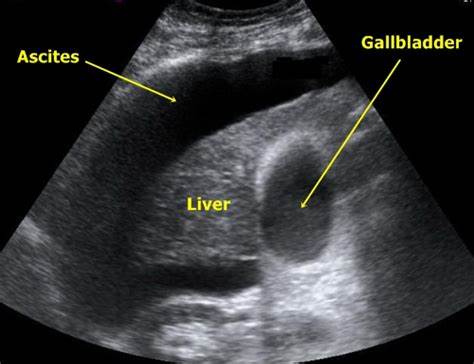

那时患者总觉得人特别累、腹胀、食欲不振。住院过程中,发现腹水:按照肝病的理论,出现腹水的慢性肝病,结合B超检查,考虑肝硬化失代偿期。

肝硬化腹水

肝硬化腹水的B超影像表现